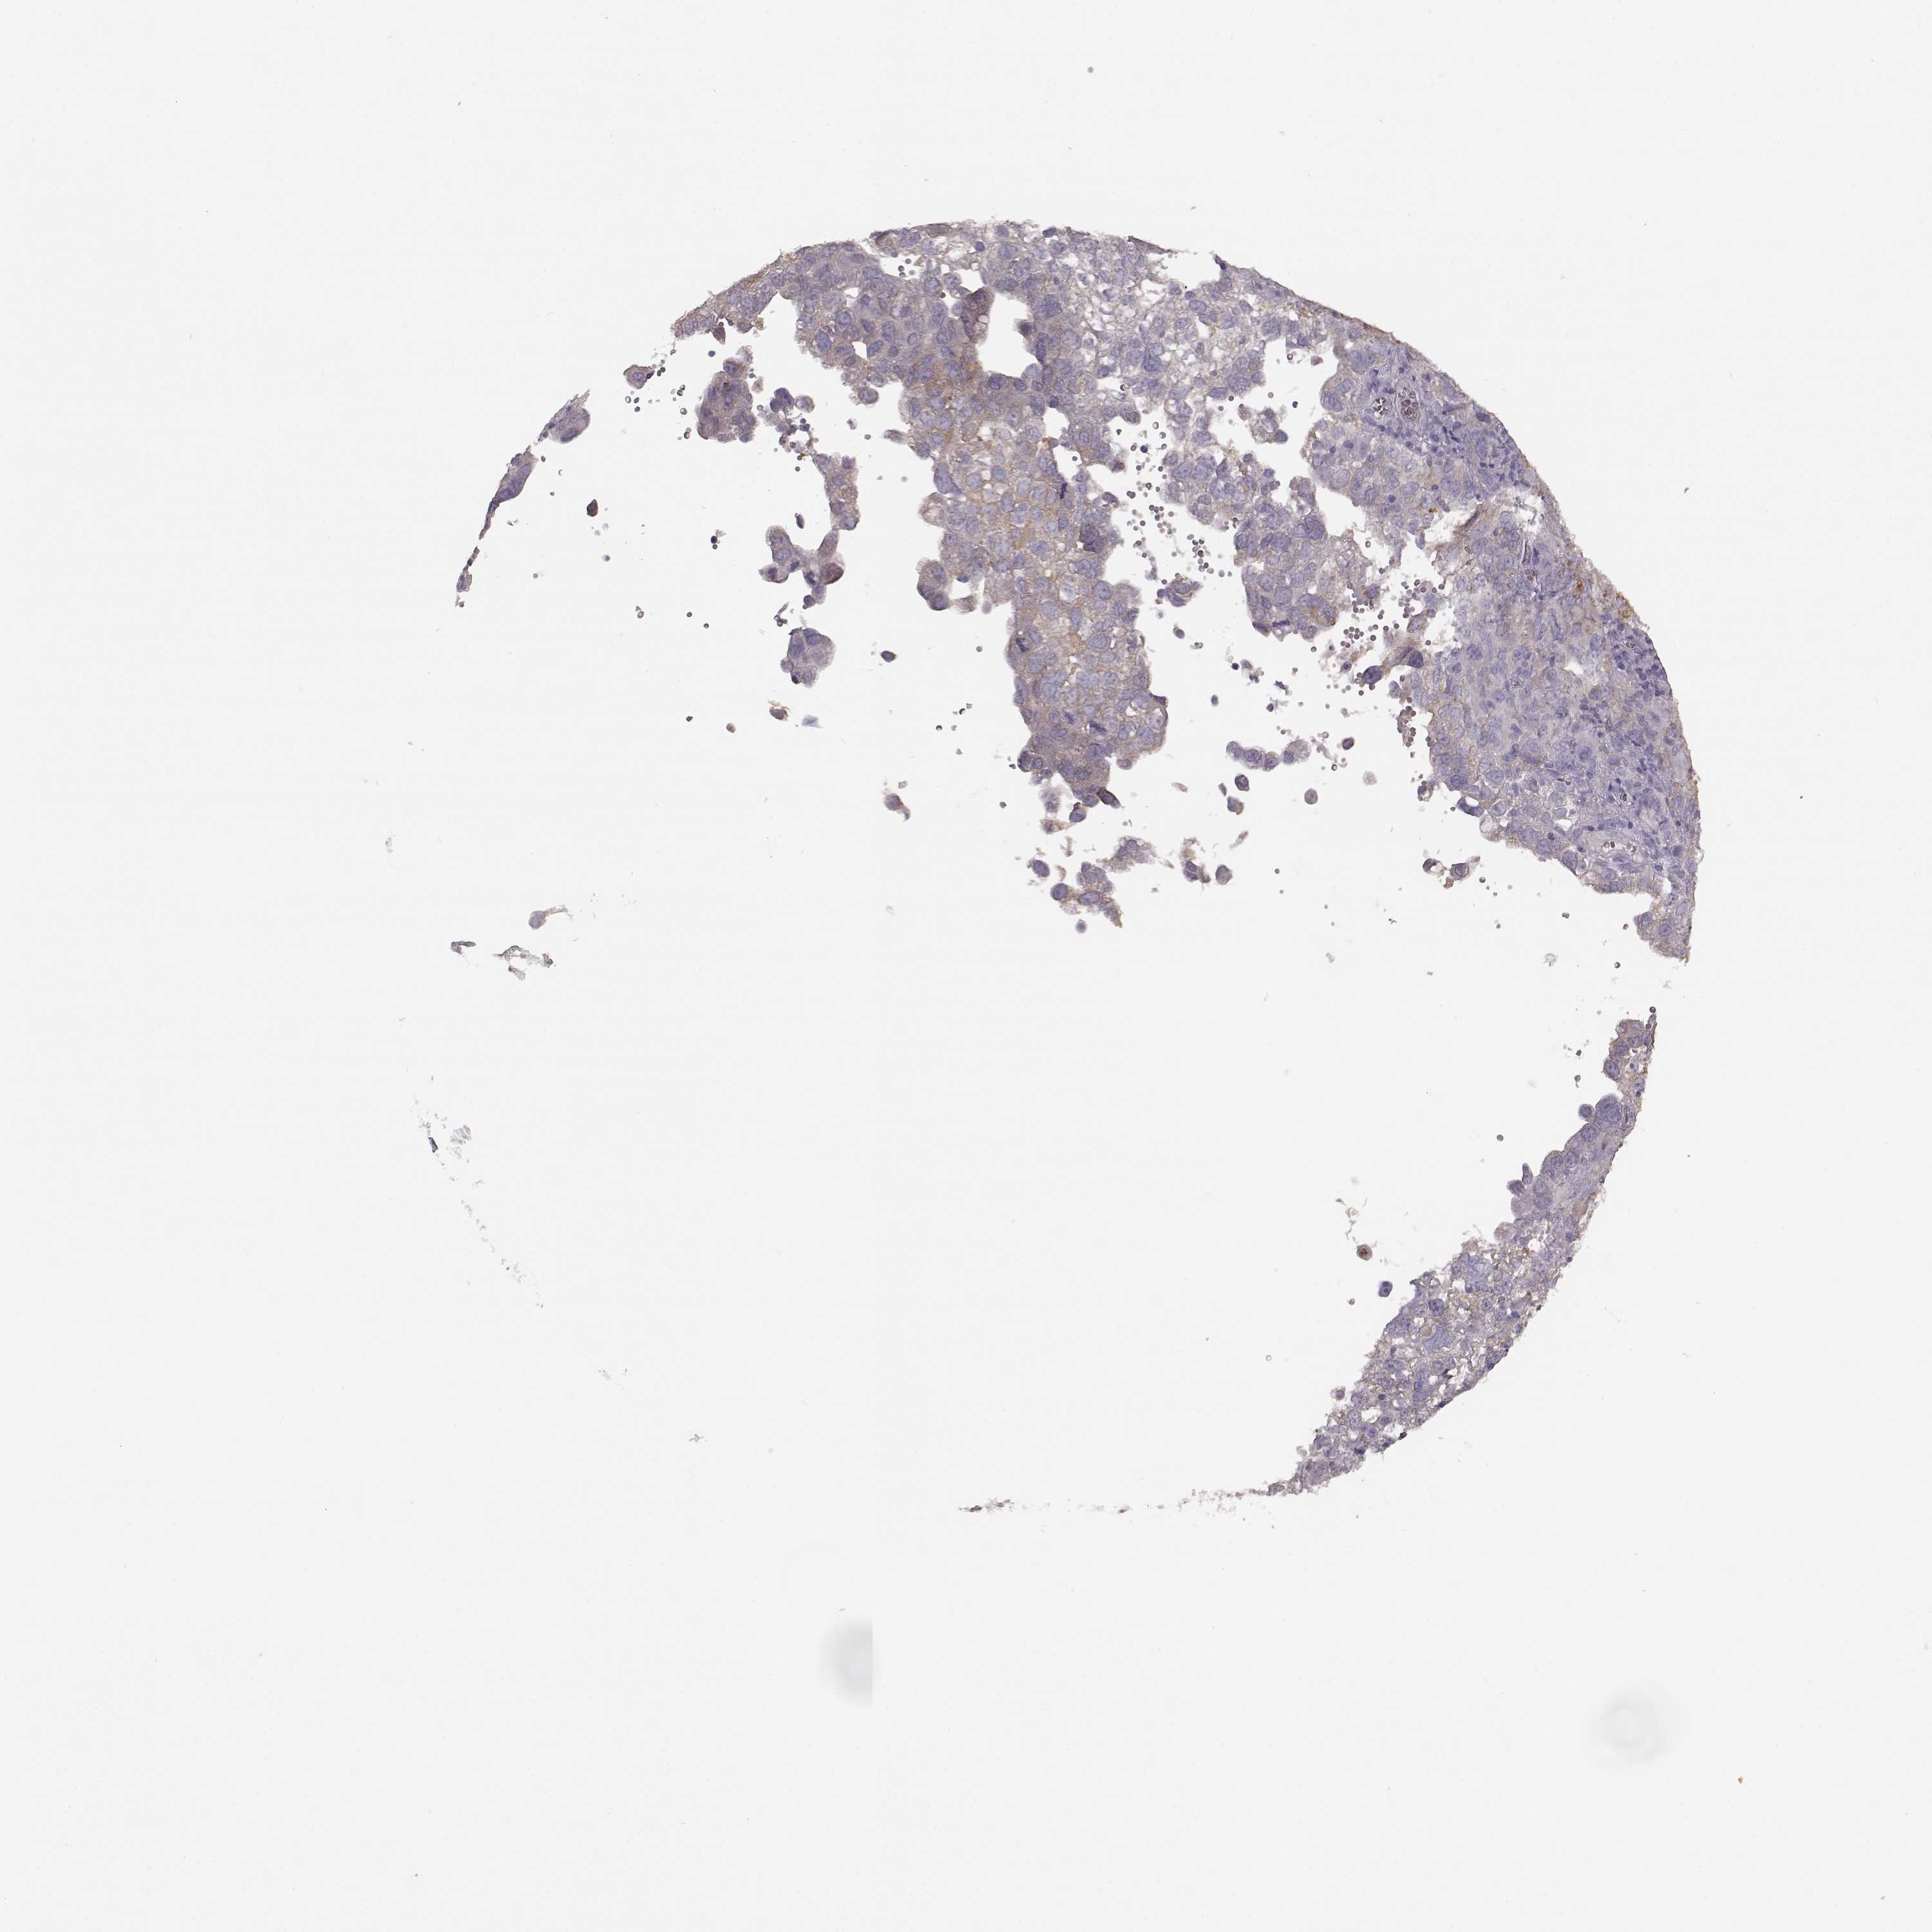

CERVICAL CANCER - Protein expressioni

A mouse-over function shows sample information and annotation data. Click on an image to view it in a full screen mode. Samples can be filtered based on level of antibody staining by selecting one or several of the following categories: high, medium, low and not detected. The assay and annotation is described here.

Note that samples used for immunohistochemistry by the Human Protein Atlas do not correspond to samples in the TCGA dataset.

Antibody stainingi

Antibody staining in the annotated cell types in the current human tissue is reported as not detected, low, medium, or high, based on conventional immunohistochemistry profiling in selected tissues. This score is based on the combination of the staining intensity and fraction of stained cells.

Each image is clickable and will lead to virtual microscopy that enables deeper exploration of all samples and also displays staining intensity scores, fraction scores and subcellular localization as well as patient and tissue information for each sample.

Antibody HPA045339

Staining

High

Medium

Low

Not detected

Intensity

Strong

Moderate

Weak

Negative

Quantity

>75%

75%-25%

<25%

None

Location

Nuclear

Cytoplasmic/membranous

Cytoplasmic/membranous,nuclear

Squamous cell carcinoma, NOS

Adenocarcinoma, NOS